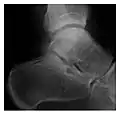

The greater tuberosity of the humerus is also an illustrative location of occult fractures. The osseous injury may follow seizures, glenohumeral dislocation, forced abduction, or direct impaction. They are commonly discovered on MRI in symptomatic patients with suspicion of rotator cuff tear. Coronal images are best suited for detection. They appear as crescentic oblique lines surrounded by a bone marrow edema pattern (Figure 5). The rotator cuff must be inspected since associated ligamentous lesions are common. In the ankle, malleoli and tarsal bones should be checked carefully for any cortical disruptions and radiolucent lines that may reveal a fracture. Awareness of the exact location of the pain will help direct the attention of the interpreter when searching for very subtle signs of fracture (Figure 6).[1]

Figure 6: Subtle anterior talar fracture in a 39-year-old man presenting with ankle pain after a fall. (a) Anteroposterior radiograph shows a subtle oblique radiolucent line through the talus (white arrows). (b) Sagittal CT reformation confirms the presence of an anterior talar fracture with cortical offset (black arrow). Avulsion fractures, which consist of a detached bone fragment resulting from a ligament or tendon pulling away from the bone, may also present with subtle radiographic signs. Tiny osseous fragments near the presumed attachment site of a ligament suggest this diagnosis. Common sites are the lateral tibial plateau (the Segond fracture), the spinal tuberosity of the tibia resulting from anterior cruciate ligament avulsion, and the ischial tuberosity.[1]